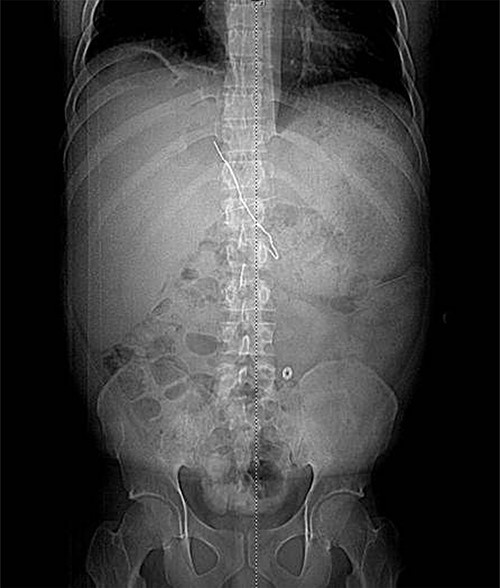

The patient presented after ingestion of an open paperclip and insertion of a sewing needle into his ventral hernia ~4 months prior. He presented with fever, tachycardia and abdominal pain, but a benign abdominal exam, noting only mild tenderness over his large, reducible ventral hernia. A computed tomography (CT) of the abdomen and pelvis showed a 10-cm metallic foreign body extending from the mid transverse colon to the left hepatic lobe with an intrahepatic abscess measuring 9.1 x 7.3 cm (Figs 1–3). In addition, there were two other metallic foreign bodies: one extraluminal in the left upper quadrant, which was stable from prior imaging, and a subcutaneous foreign body above the hernia contents. Blood cultures grew streptococcus intermedius and he was started on broad spectrum antibiotics (piperacillin–tazobactam). The case was discussed with Interventional Radiology (IR) and deemed reasonable for attempt at percutaneous abscess drainage and trans-hepatic foreign body retrieval.

Fluoroscopic image obtained intraoperatively demonstrating removal of the metallic foreign body